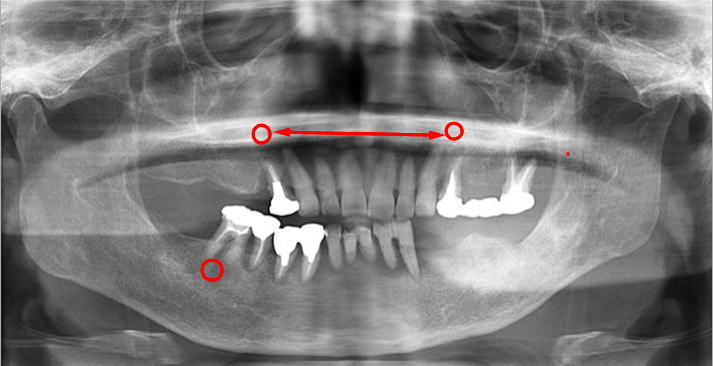

上の2枚のレントゲンは上下奥歯の咬合関係が無く左右前後の咬合崩壊が起きています。

この患者様は、〇 の歯以外は全て抜歯せざるを得ない状態でした。

歯がない箇所の放置は、咬合崩壊を必ず起こします。

義歯が使えないとの主訴で来院されました。左右、前後、歯の高さは完全に崩壊。

この噛み合わせで義歯を作ったところで、噛み合わせはズレ、義歯を入れるスペースも不足(↕)しています。

義歯を新製はしたが「噛み辛い」「ガタつく」「痛い」は、咬合関係の崩壊を修正せず、基準を無視し新製してしまった症状と大いに考えられます。